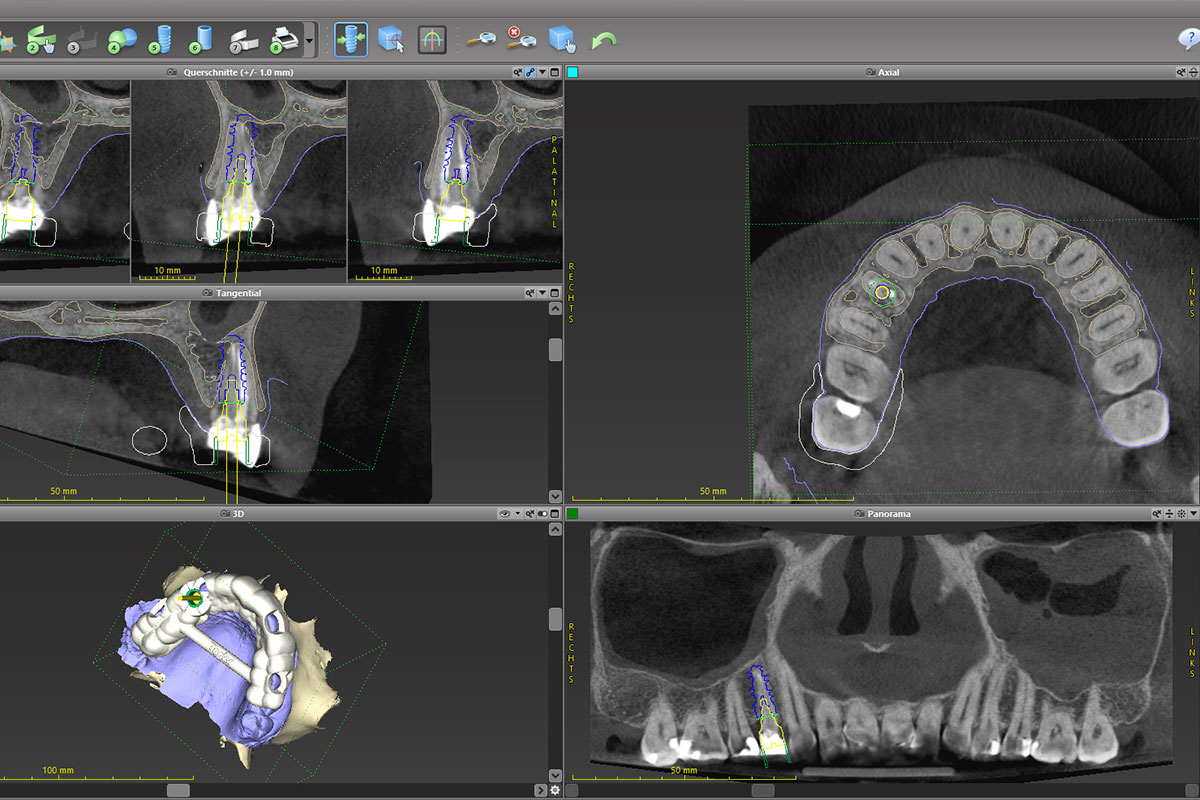

Bei einem Sofortimplantat wird die Behandlung vorab mit Hilfe eines 3D-Röntgens, dem sogenannten DVT-Scans, geplant. So kann die spätere Krone bereits im Voraus designt und hergestellt werden. Insbesondere wenn es sich um einen sichtbaren Frontzahn handelt, ist dies ein großer Gewinn für die Ästhetik und den Komfort.

- Digitale Planung: Mithilfe eines DVT-Scans wird die Behandlung exakt vorbereitet. Implantatposition und spätere Krone werden präzise geplant.